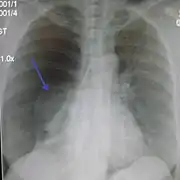

Chest X-ray

A plain chest radiograph, ideally with the X-ray beams being projected from the back (posteroanterior, or "PA"), and during maximal inspiration (holding one's breath), is the most appropriate first investigation.[30] It is not believed that routinely taking images during expiration would confer any benefit.[31] Still, they may be useful in the detection of a pneumothorax when clinical suspicion is high but yet an inspiratory radiograph appears normal.[32] Also, if the PA X-ray does not show a pneumothorax but there is a strong suspicion of one, lateral X-rays (with beams projecting from the side) may be performed, but this is not routine practice.[15][19]

Chest X-ray showing a pneumothorax on the right (left in the image), where the absence of lung markings indicates that there is free air inside the chest

It is not unusual for the mediastinum (the structure between the lungs that contains the heart, great blood vessels, and large airways) to be shifted away from the affected lung due to the pressure differences. This is not equivalent to a tension pneumothorax, which is determined mainly by the constellation of symptoms, hypoxia, and shock.[13]

The size of the pneumothorax (i.e. the volume of air in the pleural space) can be determined with a reasonable degree of accuracy by measuring the distance between the chest wall and the lung. This is relevant to treatment, as smaller pneumothoraces may be managed differently. An air rim of 2 cm means that the pneumothorax occupies about 50% of the hemithorax.[15] British professional guidelines have traditionally stated that the measurement should be performed at the level of the hilum (where blood vessels and airways enter the lung) with 2 cm as the cutoff,[15] while American guidelines state that the measurement should be done at the apex (top) of the lung with 3 cm differentiating between a "small" and a "large" pneumothorax.[33] The latter method may overestimate the size of a pneumothorax if it is located mainly at the apex, which is a common occurrence.[15] The various methods correlate poorly but are the best easily available ways of estimating pneumothorax size.[15][19] CT scanning (see below) can provide a more accurate determination of the size of the pneumothorax, but its routine use in this setting is not recommended.[33]

Not all pneumothoraces are uniform; some only form a pocket of air in a particular place in the chest.[15] Small amounts of fluid may be noted on the chest X-ray (hydropneumothorax); this may be blood (hemopneumothorax).[13] In some cases, the only significant abnormality may be the "deep sulcus sign", in which the normally small space between the chest wall and the diaphragm appears enlarged due to the abnormal presence of fluid.[16]